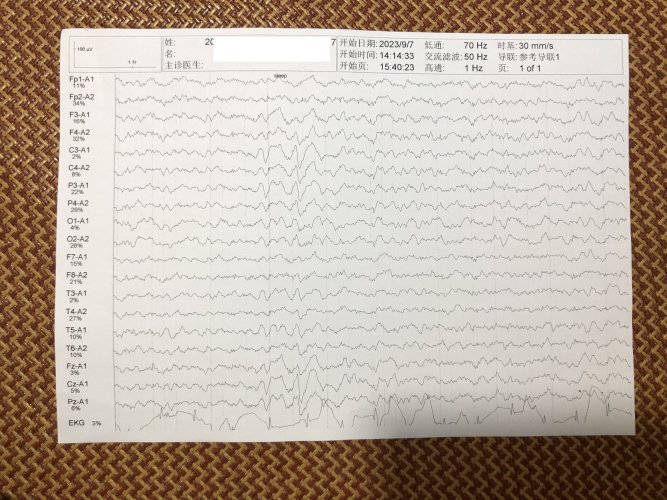

反馈下情况,孩子在国内的医院已经进行过一轮全面检测,没发现什么问题,但是现象是存在的。医生也没什么办法。医生说核磁共振和脑电图没问题,我们也不是很看得懂,各位如果懂的,请指点一下。另外进行了部分基因检测,没发现异常。下一步,我们国庆后打算去更权威的医院去碰碰运气。谢谢各位!

513.6 KB 查看: 103

532.8 KB 查看: 142

551 KB 查看: 132

526.8 KB 查看: 133

510 KB 查看: 103

506.4 KB 查看: 124

495.7 KB 查看: 165

435.1 KB 查看: 151